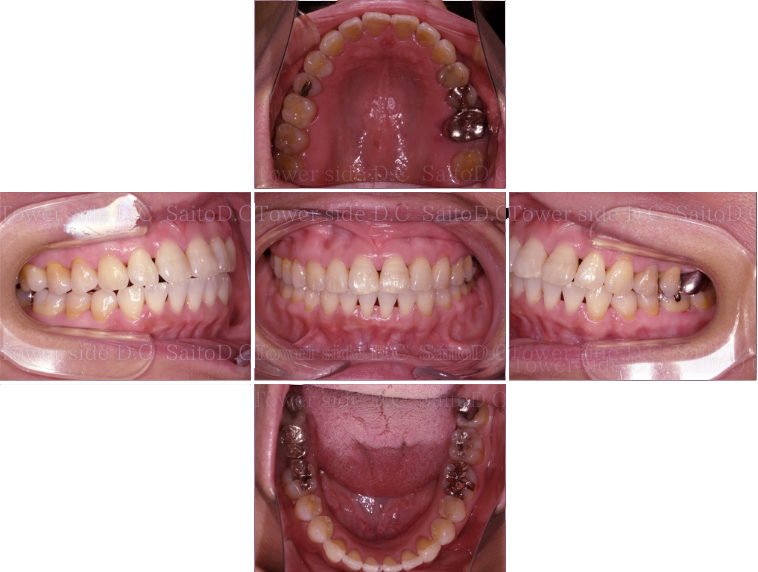

症例8CASE 8

|20代歳(女性)|

インビザラインエクスプレス

症例(施術前)

症例(施術後)

主訴 上顎側切歯の出っ張りを治したい

状況

• 上顎前歯叢生

• 上顎切歯口蓋側傾斜

• 下顎叢生

治療費 519,200円(税込)(自由診療)

治療期間 8ヶ月

治療内容 歯のディスキングを行い歯列を整えた。叢生は改善され、その後保定装置(リテーナー)を使用し安定している。